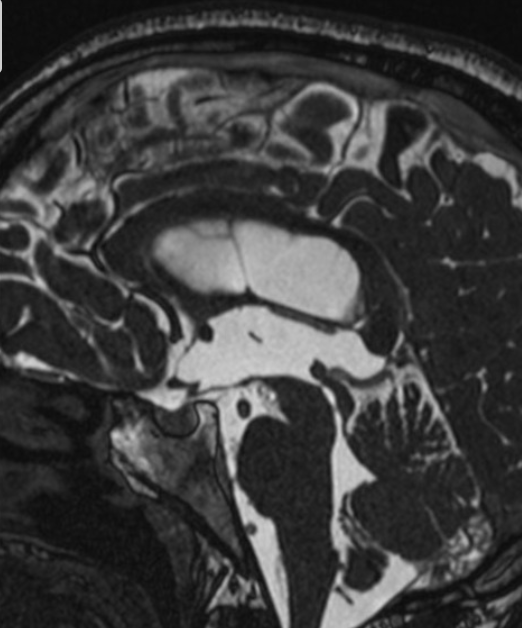

dandy walker malformation

This case illustrates a classic Dandy Walker malformation with associated aqueduct stenosis and obstructive hydrocephalus, a common associated feature

(although not part of the Dandy walker triad: